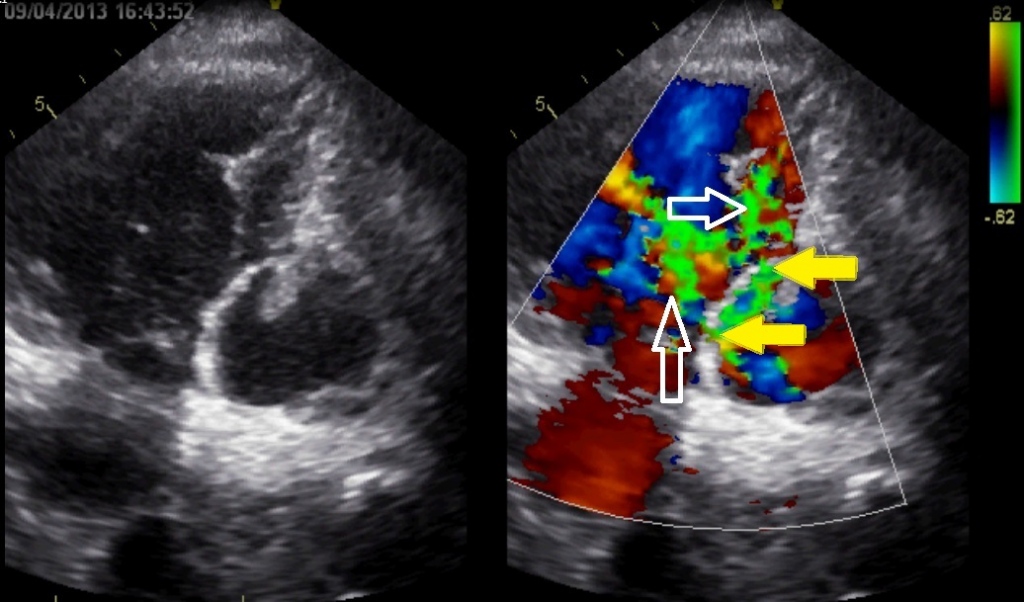

Video 2 / Figuur 2

Figuur 2: behorende bij video 2. Transthoracale echocardiografie. Apicale 4-kameropname, iets met de echotransducer gedraaid.

Er is flow te zien (met witte pijlen aangegeven) vanuit de linkerkamer naar de rechterkamer. De gele pijl geeft de plaats van de ruptuur aan.